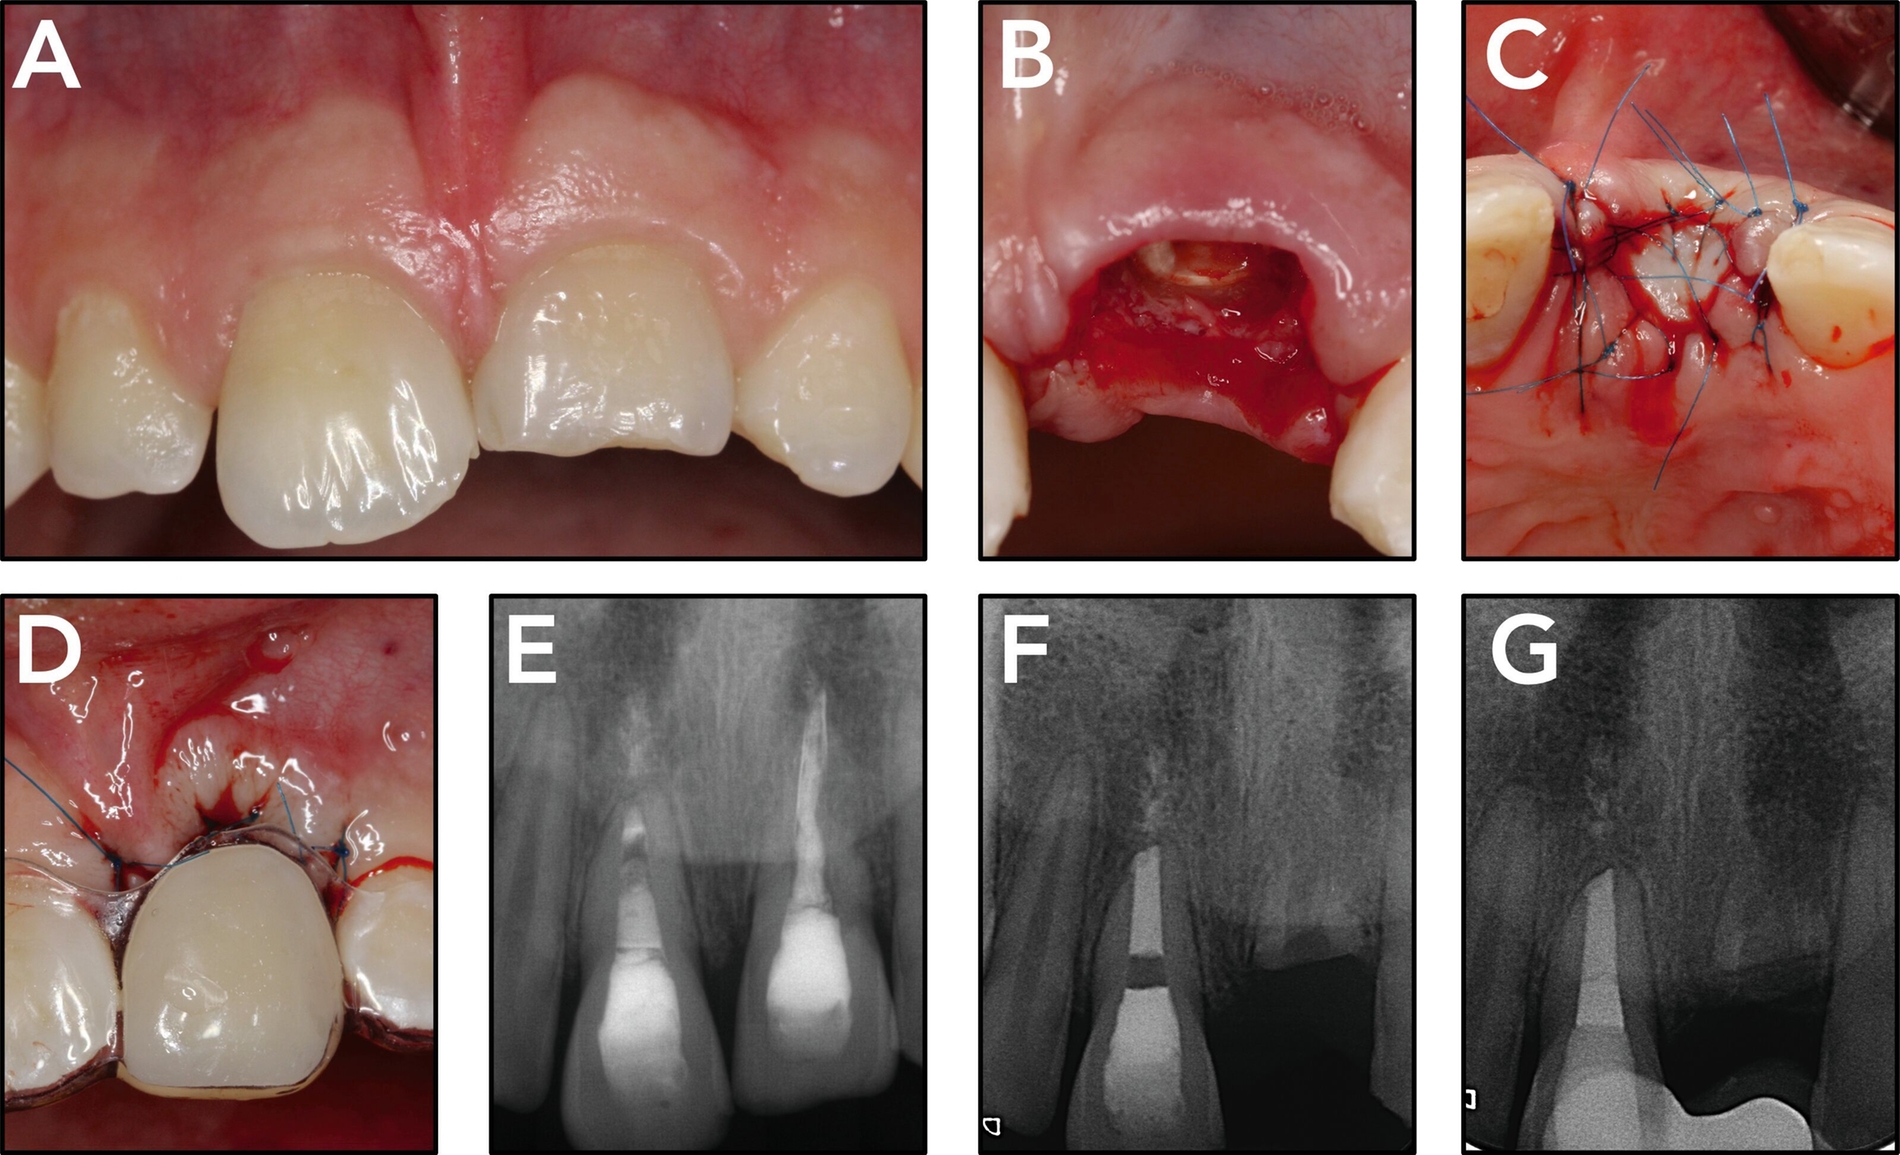

Der ankylosierte Zahn wird schonend gelöst („anluxiert“), bei Bedarf auch osteotomiert und aus seiner ursprünglichen Infraposition und/oder Verlagerung in die Okklusionsposition zum gesunden Nachbarzahn gestellt. Das Ziel dieser Maßnahme ist es, das vertikale Defizit durch die Ankylose-bedingte Wachstumshemmung aufzufangen (Abbildung 3). Je nach dem Zeitpunkt der Maßnahme und dem Verlauf kann der Zahn so vom frühen bis ins späte Wechselgebiss, in günstigen Fällen auch bis ins Erwachsenenalter, erhalten werden. Ob später ein kieferorthopädischer Lückenschluss, eine Prämolaren-Transplantation oder eine Implantation folgt, muss individuell nach der weiteren abzuschätzenden Prognose des Zahnes und nach dem Patientenwunsch entschieden werden.

Die Versorgung einer Lücke mit Zahnimplantaten nach einem dentalen Trauma wird in der Regel nach Abschluss des pubertären Wachstumsschubes erwogen oder besser noch ins frühe Erwachsenenalter verlegt. Wenn zu diesem Zeitpunkt keine Sofortimplantation zusammen mit der Zahnwurzelextraktion erfolgt, sollte die Möglichkeit der Ridge preservation geprüft werden. Wenn eine Versorgung mit Zahnimplantaten erfolgt, dann nicht in der Akutphase des Traumas, sondern nach Abheilung der Weichteilwunden und der direkten allgemeinen Traumafolgen (Abbildung 5).